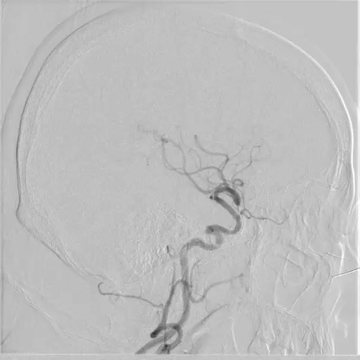

Tubridge Plus Case 4